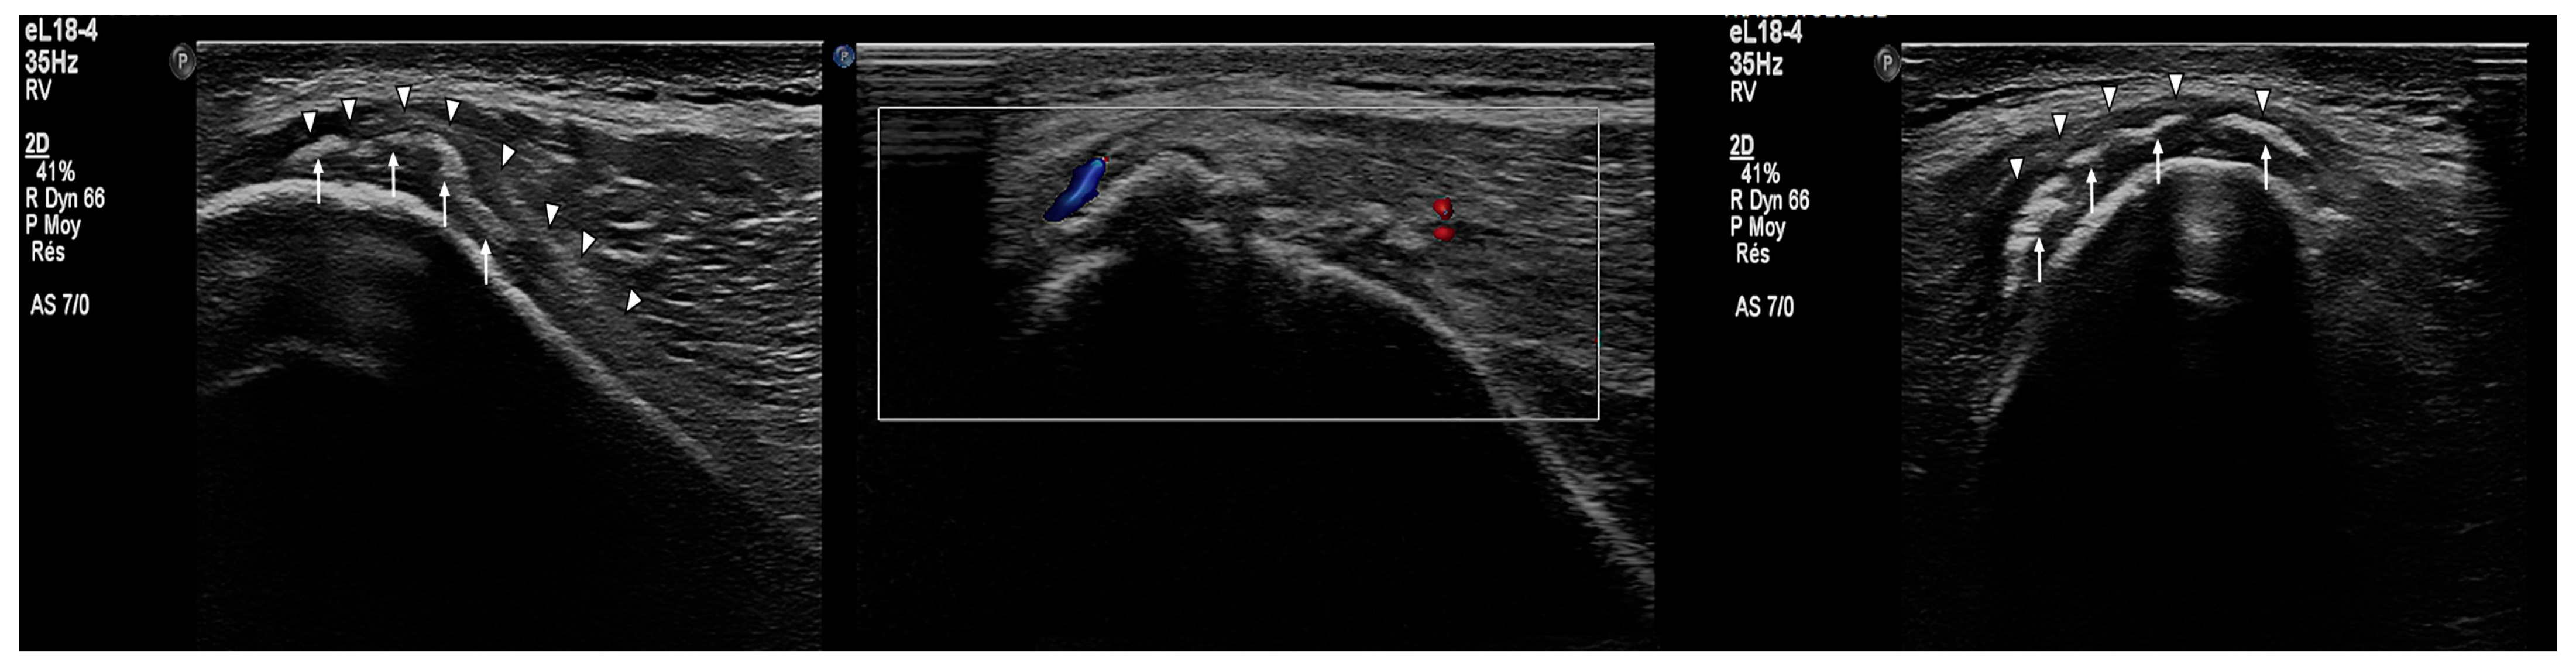

- Subperiosteal hematoma at the posterior iliac crest;

- A 20–25 mm detachment of the gluteus maximus;

- Partial involvement of the gluteus medius.